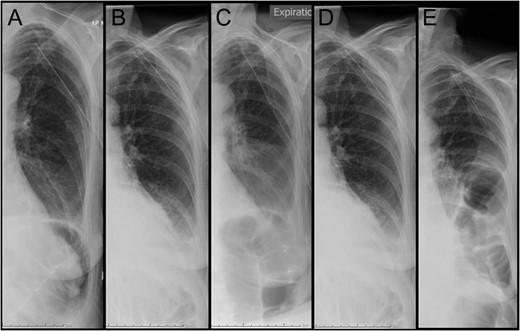

Representative coronal slice of computed tomography confirming the presence of a traumatic diaphragmatic hernia with a loop of incarcerated colon in the left hemithorax.